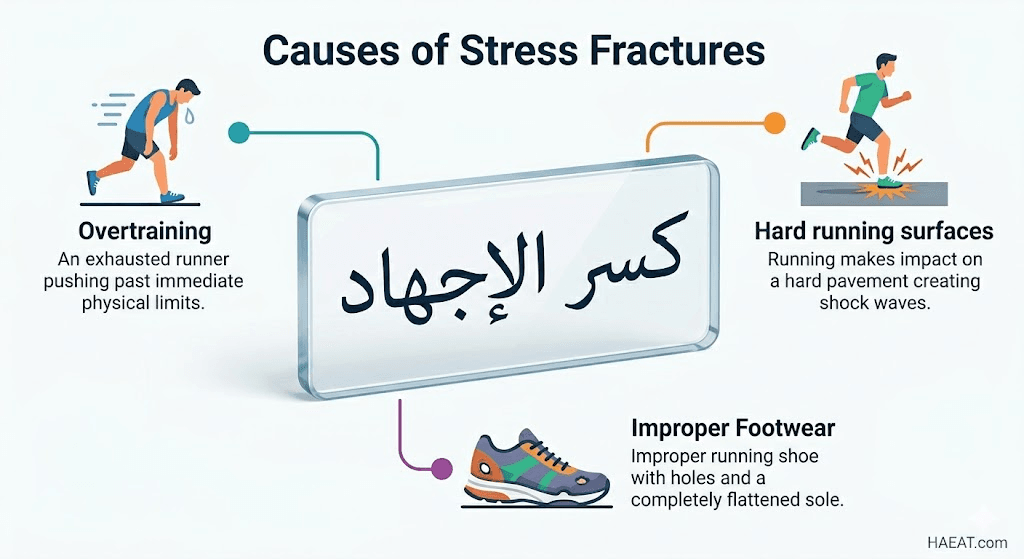

أسباب كسر الإجهاد

تعتبر أسباب هذه الإصابة مزيجاً بين الميكانيكا الحيوية الخاطئة والبيئة التدريبية، وتشير “مدونة HAEAT الطبية” إلى أن العوامل التالية هي المحرك الأساسي لحدوث الشقوق العظمية:

- الزيادة المفاجئة في شدة التمرين: رفع وتيرة النشاط أو مدته أو تكراره بشكل سريع لا يمنح العظام وقتاً كافياً للتكيف مع الأحمال الجديدة.

- تغيير الأسطح التدريبية: الانتقال المفاجئ من الجري على العشب أو المسارات اللينة إلى الأسطح الصلبة مثل الأسفلت أو الملاعب الخرسانية يزيد من قوة الارتداد.

- استخدام معدات غير مناسبة: ارتداء أحذية رياضية متهالكة فقدت قدرتها على امتصاص الصدمات، أو استخدام أحذية لا تدعم قوس القدم بشكل صحيح.

- ضعف التوازن العضلي: إرهاق العضلات المحيطة بالعظم يجعلها تفقد كفاءتها في امتصاص الطاقة الحركية، مما يضع كامل الحمل الميكانيكي على الهيكل العظمي.